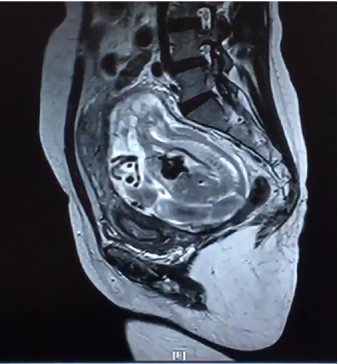

2月24日,我院产科、泌尿外科、麻醉手术科、胃肠外科、输血科等多学科合作成功救治一名腹腔妊娠特殊患者。这是我院多学科合作战胜疑难杂症的又一成功案例。近年来,作为三级甲等综合医院,樱花动漫 始终坚持以患者为中心,充分发挥综合医院的优势,积极探索研究,持续加强学科建设,不断拓展多学科合作的广度和深度,利用多学科合作为人民群众解决了很多疑难杂症,用实际行动巩固脱贫攻坚成果,助力乡村振兴,为维护人民群众的健康持续奋斗。